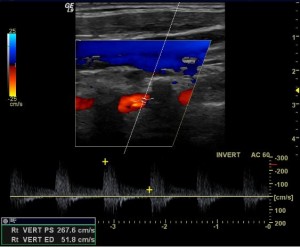

Also, there are no widely accepted duplex ultrasonography criteria for the diagnosis of vertebral artery stenosis. Some have used a peak systolic velocity of >100 cm/sec to diagnose a stenosis >50%. Also, abnormal waveforms in the mid-artery can suggest a more proximal problem: